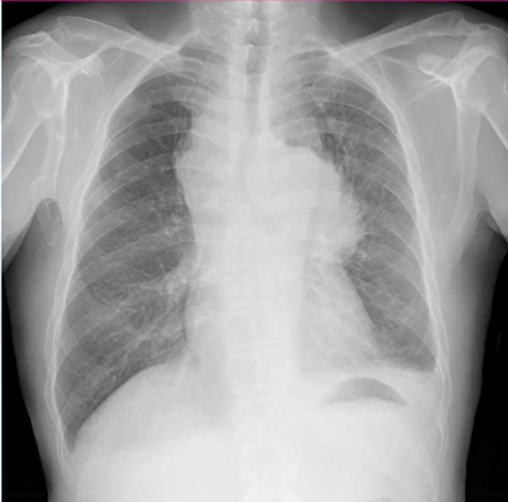

本症例のレントゲン写真の所見としては、右気管傍リンパ節腫脹、気管分枝部リンパ節腫脹、左気管傍リンパ節腫脹、左肺門リンパ節腫脹、左胸水が確認できます。

診断とすると、多発リンパ節腫脹+片側胸水ということになり、肺癌を疑います。このように腫瘤がひとかたまりに見えるものは小細胞肺癌であることが多いです。